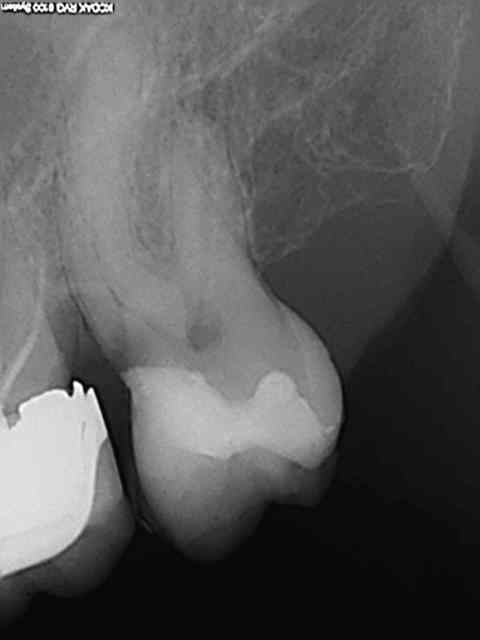

Exemple concret, de ce samedi (exceptionnellement au boulot car c'est un pote qui travaille sur Paris et qui a une semaine de vacances), j'en ai tous les jours.

la première radio date de 2011 issue d'un status inutile selon la sécu. Suspicion de reprise en mésial sous l'onlay de 27, noté sur le dossier à surveiller. Le patient appelle pour douleurs lancinantes spontanées la semaine dernière en haut au fond et à gauche exacerbées par le froid.

Diagnostic clair net et précis et par téléphone en plus : ca n'est pas du au tt merdique de la 26. Ce qui est confirmé in situ par la radio numéro 2 prise le jour meme de l'endo.

Comme à mon habitude je m'excuse d'avoir irradié le patient copieusement ( à raison de 70 kv et 0,099 s par cliché) plutot qu'un seul cliché argentique en fin de tt ( 70 kv aussi mais 1,3 s d'exposition lui) développé en fin de journée comme ca a du etre le cas pour le tt de 26 ( et m... encore raté).

Je sais pas moi mais le résultat parle de lui meme ( putain de mv2 que j'ai réussi à choper dans un 2 eme temps une fois les autres obturés)

Taille empreinte provisoire dans la foulée , l'avantage de la gutta chaude.

Vous préférez quoi dans votre bouche ? une seule radio et un tt endo comme la 26 ou 6 clichés et mon tt endo de 27 ?